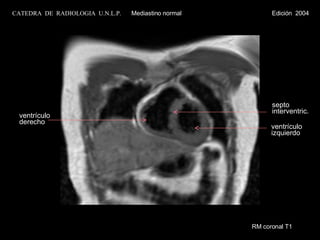

RM coronal T1 ventrículo izquierdo septo  interventric. ventrículo  derecho CATEDRA  DE  RADIOLOGIA  U.N.L.P.   Mediastino normal  Edición  2004

RM coronal T1 ventrículo izquierdo septo  interventricular ventrículo derecho a. pulmonar CATEDRA  DE  RADIOLOGIA  U.N.L.P.   Mediastino normal  Edición  2004

RM coronal T1ventrículo izquierdo septo interventric. ventrículo derecho CATEDRA DE RADIOLOGIA U.N.L.P. Mediastino normal Edición 2004

RM coronal T1ventrículo izquierdo septo interventricular ventrículo derecho a. pulmonar CATEDRA DE RADIOLOGIA U.N.L.P. Mediastino normal Edición 2004